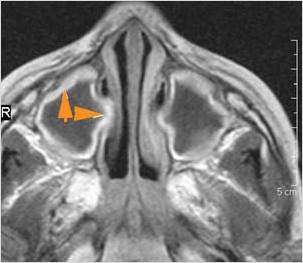

There is evidence of thrombus, thrombophlebitis or other occlusive or inflammatory process of the cavernous sinus.

There is evidence of inflammation of the distal internal carotid artery.